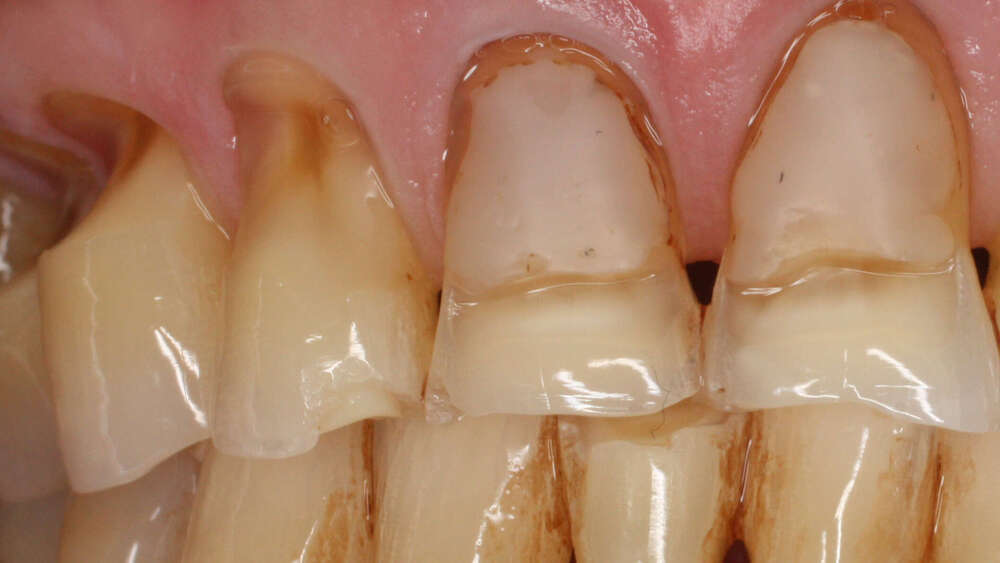

L’érosion touche de plus en plus de patients en raison de l’augmentation de la consommation de boissons acides, en particulier chez les jeunes adultes.

Son caractère insidieux fait qu’elle passe souvent inaperçue jusqu’à ce que l’émail s’amincisse, provoquant une sensibilité accrue et donnant aux dents un aspect translucide.

Pour limiter ce phénomène, il est recommandé de réduire la consommation de boissons acides, d’éviter de se brosser les dents immédiatement après leur ingestion et de privilégier une hydratation à l’eau. Lorsqu’une érosion est déjà présente, un traitement peut consister à appliquer des agents reminéralisants pour renforcer l’émail, puis, si nécessaire, à restaurer les surfaces atteintes grâce à des composites ou à des facettes en céramique qui permettent de redonner épaisseur, protection et esthétique au sourire.